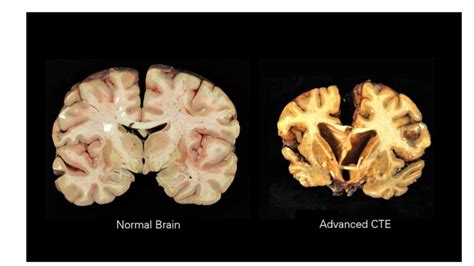

CTE and DNA Damage: How Head Trauma Triggers Brain Inflammation and Neurodegeneration